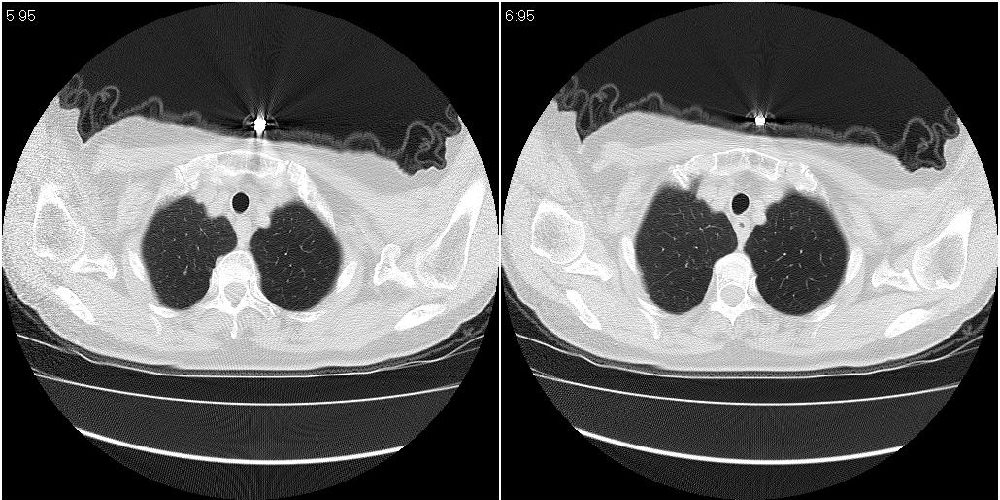

女性,72岁。去年9月份发现肺部病变,诊为肺结核并进行正规治疗至今,但复查后发现ct表现几乎没有变化。

右侧中叶支气管明显狭窄,建议行纤支镜检查!

右中间段支气管局限性狭窄,右中叶支气管亦稍显狭窄,但并未见明显占位表现,半年多了,无变化也许是好事,可能为炎性狭窄,建议继续随访。

双肺继发型tb并右中叶内膜tb,轻度支扩,左下胸膜肥厚粘连。

右中叶炎性改变,支气管狭窄但较光滑,占位可能性不大。

右中间段支气管局限性狭窄,右中叶支气管亦稍显狭窄.

双肺继发性肺结核并右肺中叶节段性肺不张,左下胸膜肥厚粘连。

右肺中叶节段性肺不张,考虑结核或慢性炎症,建议做纤支镜检查。

双肺继发性肺结核并右肺中叶节段性肺不张